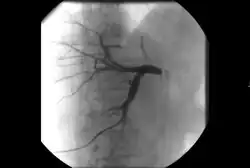

Технология диализатора изначально опережала возможности врачей применять ее к пациентам. В 1920-х годах был создан первый диализный катетер с использованием тонких хрупких стеклянных трубок. Ранние методы требовали хирургического разреза для доступа к крупным сосудам, что было сопряжено с большим риском сильного кровотечения. Первый относительно постоянный и надежный доступ для диализа — тефлоновый шунт Скрибнера — был изобретен почти 40 лет спустя и позволил пациенту с почечной недостаточностью прожить еще 11 лет. По мере того, как медицина и хирургия становятся все более совершенными, в настоящее время больше пациентов живут с хроническим заболеванием почек, чем когда-либо прежде. Наиболее распространенным видом диализа в Соединенных Штатах является гемодиализ, который может проводиться через несколько типов сосудистого доступа. Предпочтительным методом является артериовенозная фистула (АВФ). Артериовенозные фистулы создаются хирургическим путем путем прямого соединения артерии и вены, чаще всего на руке. Артериовенозный трансплантат (АВТ) работает по тому же принципу, но заполняет зазор между артерией и веной с помощью медицинского протезного шунта. Со временем изменение механики потока может привести к изменениям в пораженных сосудах. Сужение сосудов, тромбоз, аневризмы и псевдоаневризмы являются частыми осложнениями, встречающимися в течение срока службы артериовенозной фистулы или артериовенозной троакарной тугоухости. Интервенционные радиологи могут использовать ангиографию для оценки этих структур (обычно называемую истулограммой) и лечить дисфункциональный доступ с помощью ангиопластики, стентирования и тромбэктомии. Большинству пациентов требуются регулярные обследования и лечение для поддержания работоспособности доступа. По возможности предпочтение отдается артериовенозным фистулярным трубкам, а не артериовенозным ангиопластикам, поскольку они вызывают относительно меньше осложнений и обеспечивают большую проходимость. Инициатива Fistula First направлена на повышение осведомленности врачей и пациентов о преимуществах первой попытки гемодиализа через фистулу.[42] Существует несколько устройств (эндо АВФ), которые используются интервенционными радиологами для чрескожного создания свищей минимально инвазивным способом.